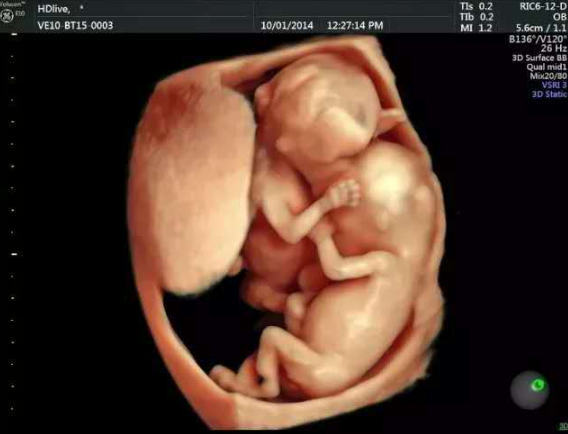

(图片来源网络,侵删)